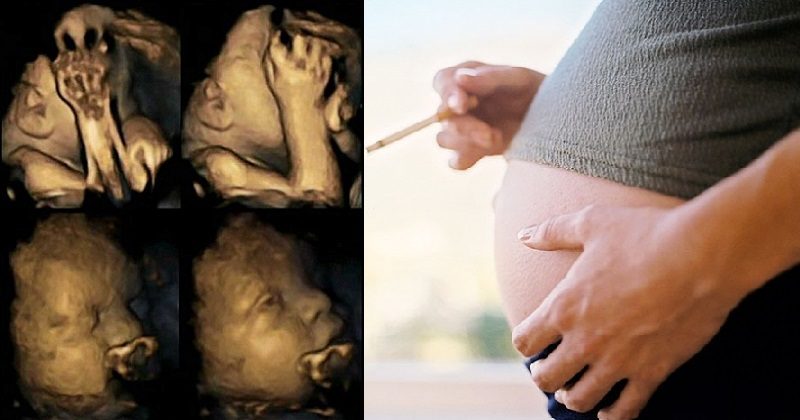

4D Ultrasound Scan Shows Effects Of Smoking On Babies During Pregnancy

Now researchers believe they can show the effects of smoking on babies in the womb using 4D ultrasound scans – and use the images to encourage mothers who are struggling to give up. Dr Nadja Reissland has studied moving 4D scan images and recorded thousands of tiny movements in the womb. Her study, conducted at the James Cook University Hospital in Middlesbrough.

Dr Nadja Reissland scanned babies between weeks 24 and 36 of pregnancy, and showed that babies carried by women who smoked appeared to move their mouths and touch their faces more than non-smokers’ babies.